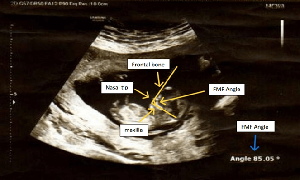

Objective: This study aims to establish normative reference ranges for FMF angle measurements in North Indian fetuses during first trimester (11-13+6 weeks of gestation) and assess its clinical significance. Design: A prospective observational study was conducted at GSVM Medical College, Kanpur, involving 161 North Indian pregnant females. Methods: Transabdominal ultrasound measurements of FMF angle were obtained using standardized mid-sagittal imaging techniques. The relationship between FMF angle and crown-rump length (CRL), gestational age, and maternal factors was analyzed using statistical models. Results: The mean FMF angle was 83.90° (SD = 1.76°), with a range of 80.0° to 87.3°. A strong inverse correlation was observed between FMF angle and CRL (r = -0.789, p <.001), confirming a gestational age-dependent decline. No significant influence of maternal age (p =.574) or gravida status (p =.233) was found on FMF angle measurements. The 5th to 95th percentile reference range for FMF angle was established as 81.3° to 86.5°, providing a clinically relevant baseline for North Indian populations. Conclusion: FMF angle is a stable and reproducible prenatal screening parameter in North Indian pregnancies. The study establishes normative data essential for refining regional first- trimester screening protocols and improving early detection of fetal anomalies.